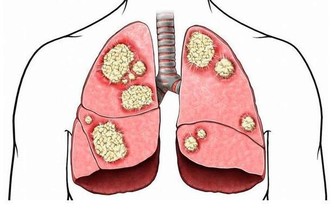

三、助淋巴流動脾臟是身體最大的淋巴器官,流動的方式是靠着肌肉收縮,

如果不往左側睡淋巴會停擺,

因此靠左側睡淋巴液會因重力流入脾臟,循環更加有效率也能幫助毒素排出,隨着毒素

一一排出我們的身體,代表我們會越來越健康!